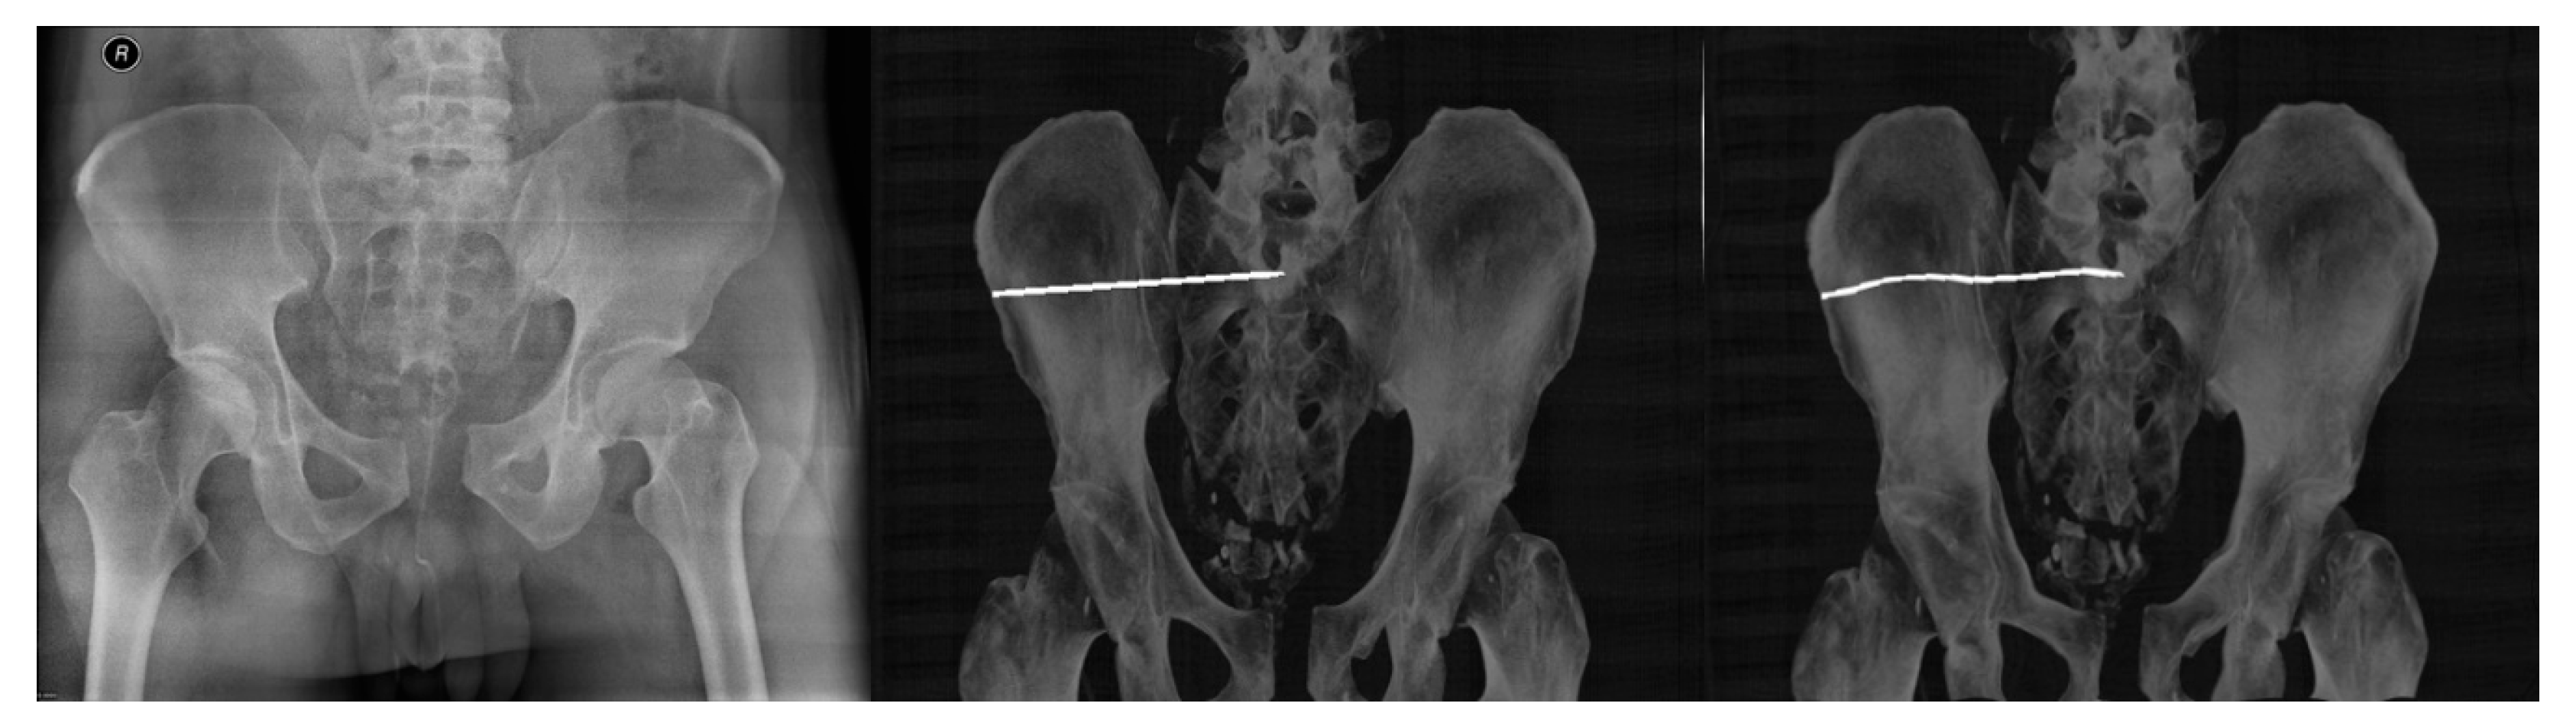

- Multimodal (X-ray/CT) image registration for optimal CT slice selection according to the reference X-ray image.

- Multimodal image registration of DRR projections to a reference X-ray image